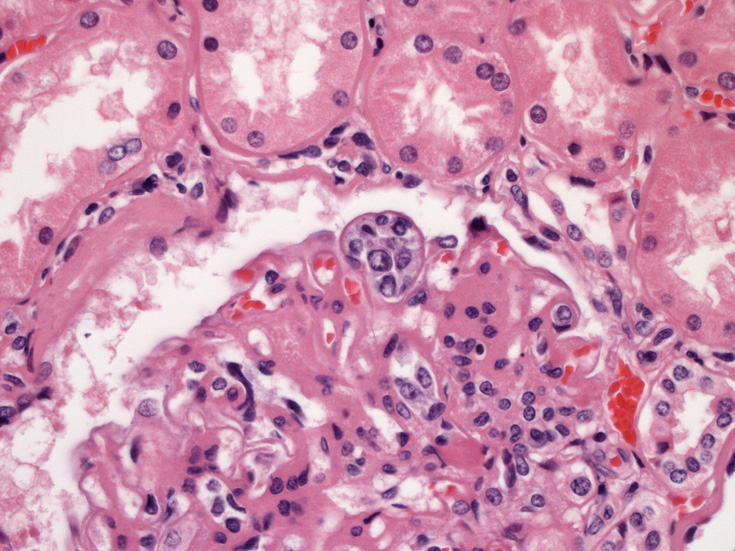

腎臓;糸球体係蹄内に腫瘍細胞が増殖するほか細腎動脈にもみとめられる。